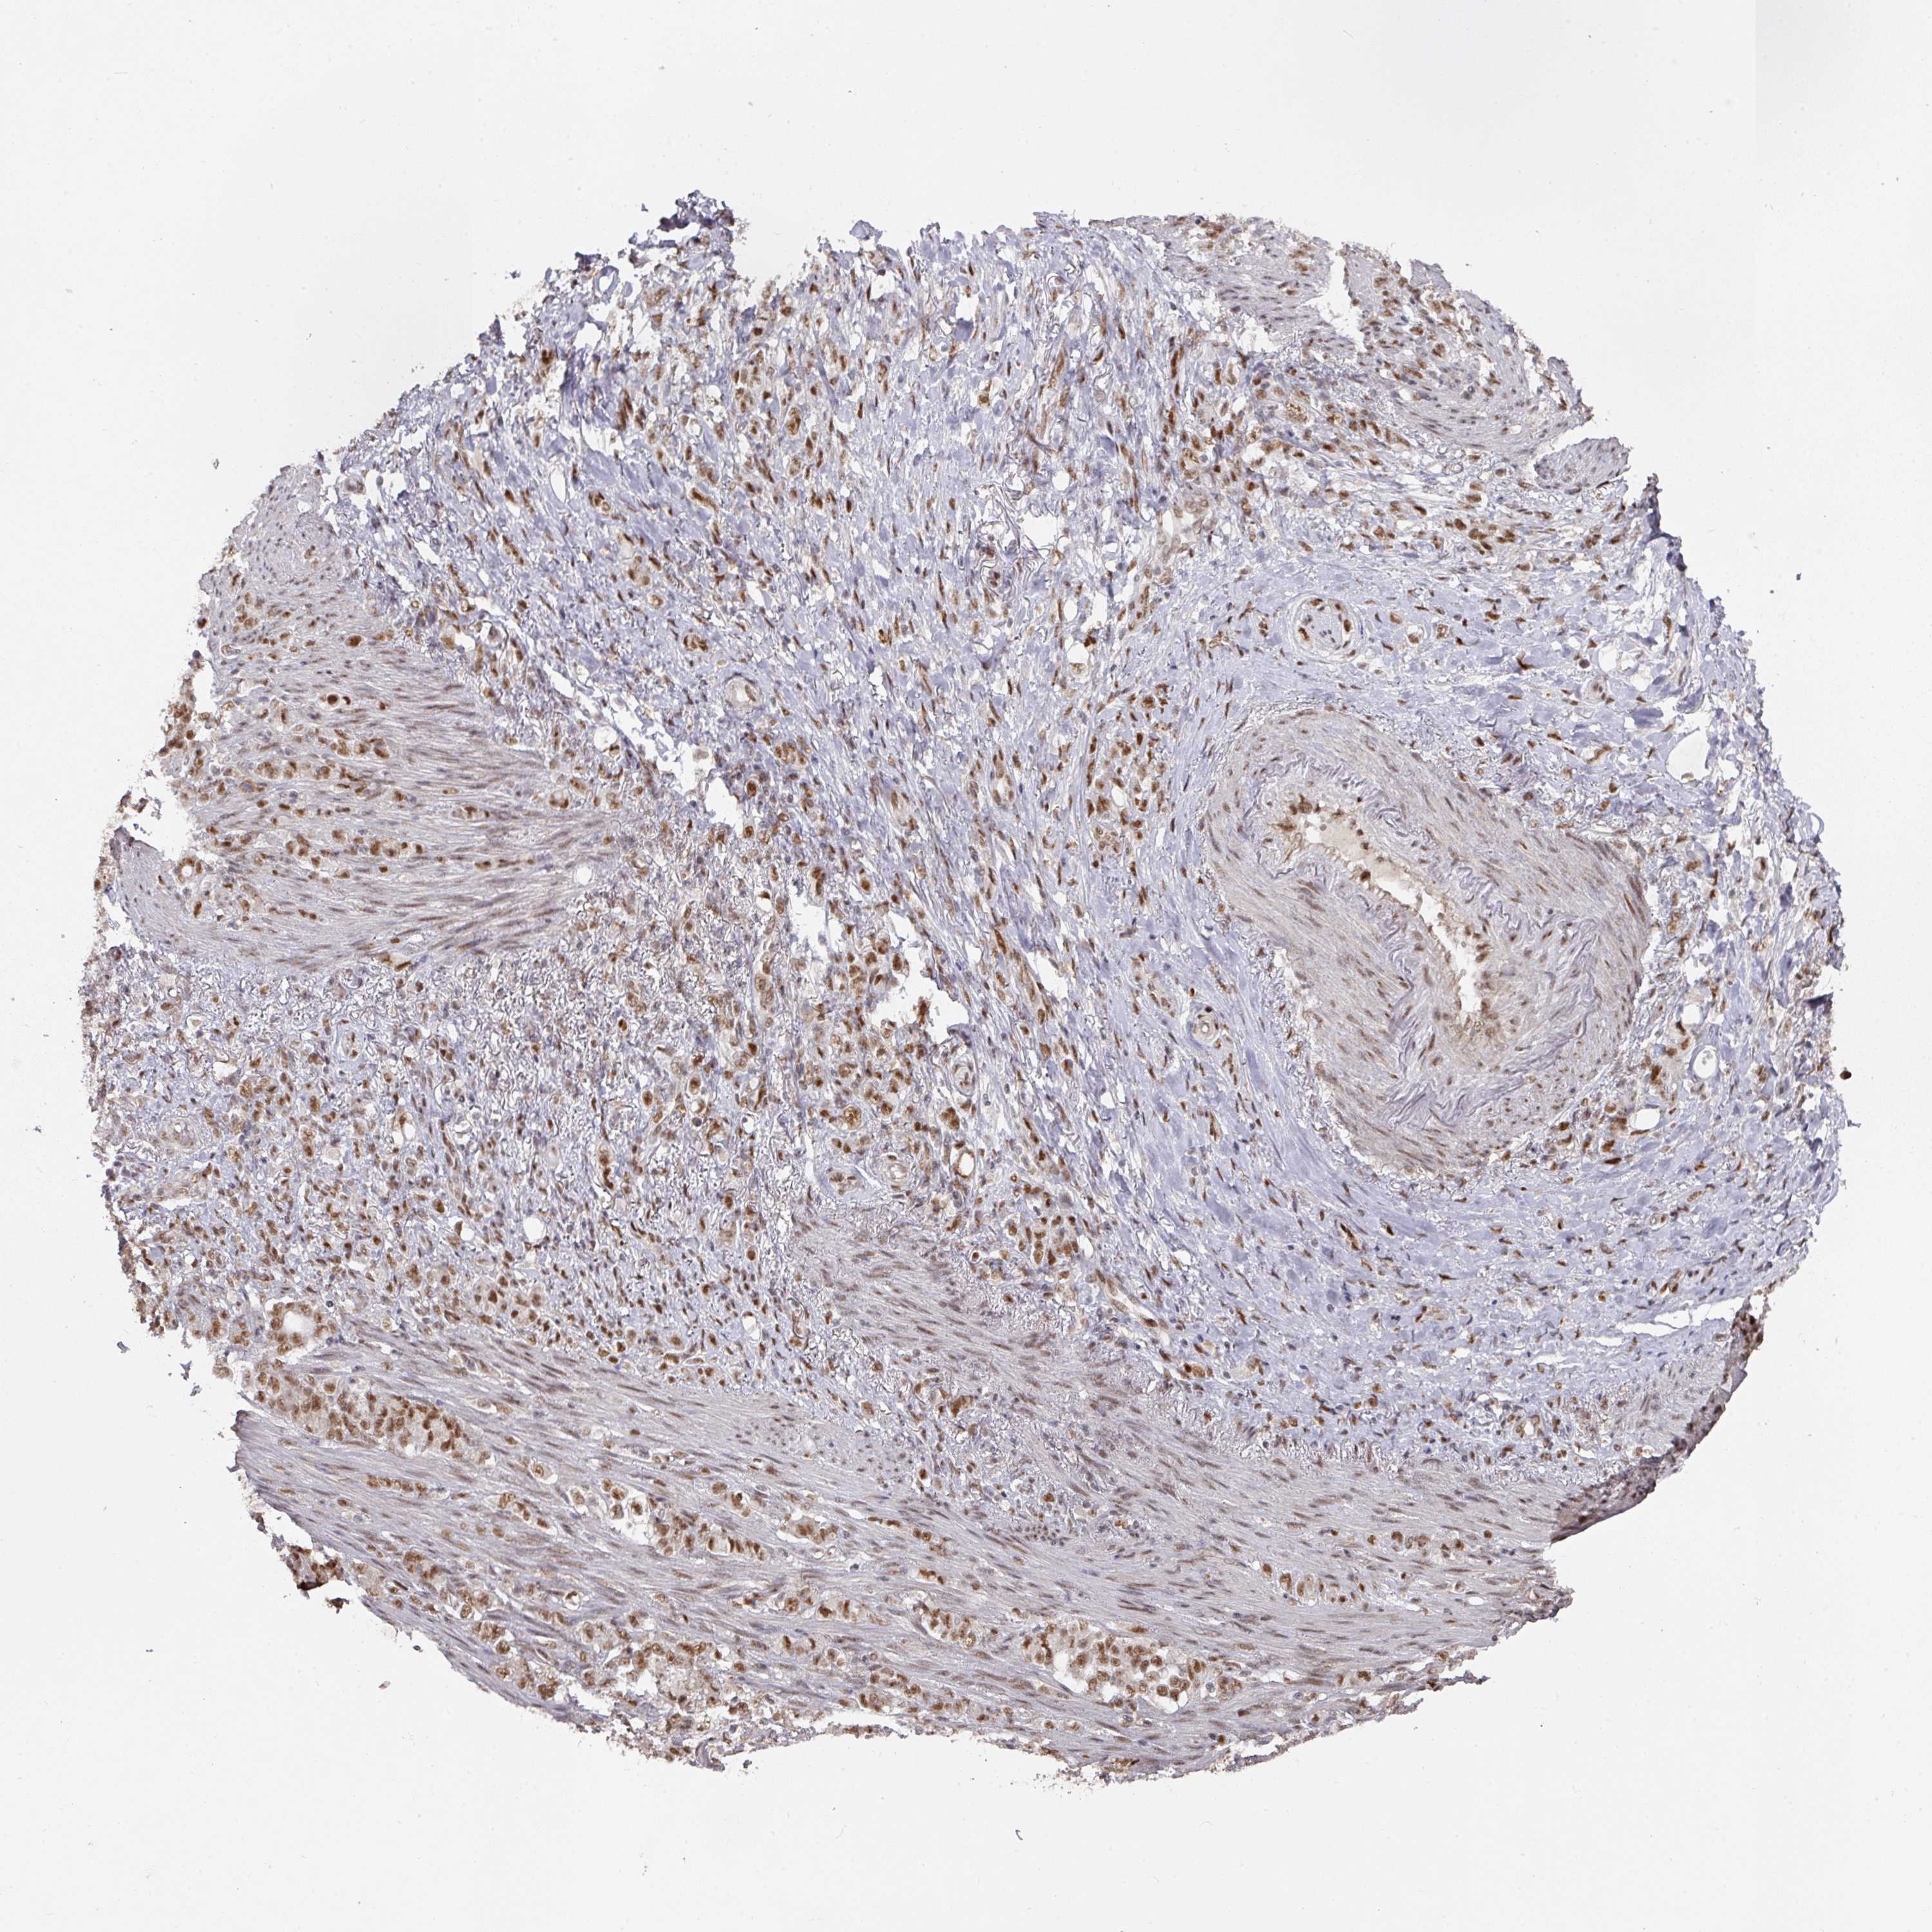

STOMACH CANCER - Protein expressioni

A mouse-over function shows sample information and annotation data. Click on an image to view it in a full screen mode. Samples can be filtered based on level of antibody staining by selecting one or several of the following categories: high, medium, low and not detected. The assay and annotation is described here.

Note that samples used for immunohistochemistry by the Human Protein Atlas do not correspond to samples in the TCGA dataset.

Antibody stainingi

Antibody staining in the annotated cell types in the current human tissue is reported as not detected, low, medium, or high, based on conventional immunohistochemistry profiling in selected tissues. This score is based on the combination of the staining intensity and fraction of stained cells.

Each image is clickable and will lead to virtual microscopy that enables deeper exploration of all samples and also displays staining intensity scores, fraction scores and subcellular localization as well as patient and tissue information for each sample.

Antibody HPA051587

Antibody CAB026384

Staining

High

Medium

Low

Not detected

Intensity

Strong

Moderate

Weak

Negative

Quantity

>75%

75%-25%

<25%

None

Location

Nuclear

Cytoplasmic/membranous

Cytoplasmic/membranous,nuclear

Adenocarcinoma, NOS